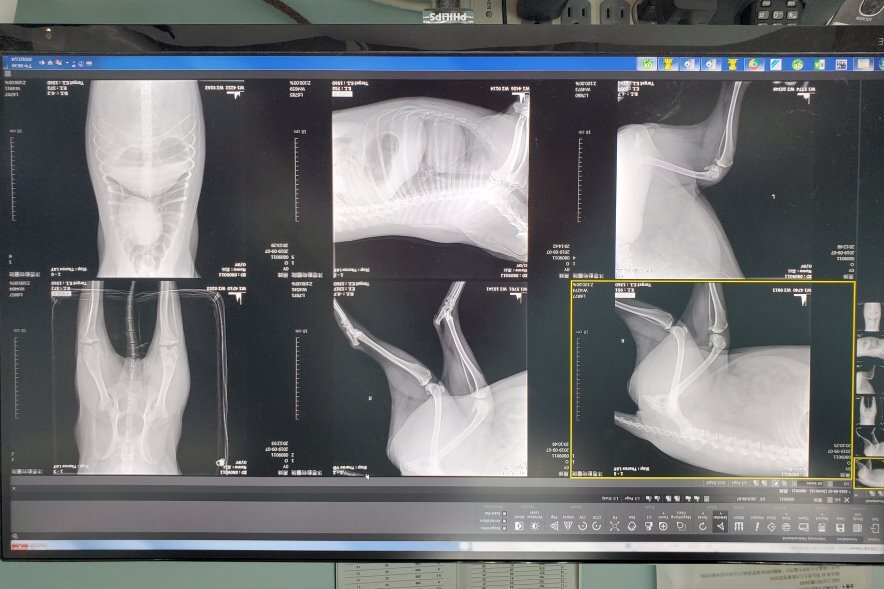

黑妹的是體型較大的女生,常常仗著身材優勢,欺負、威壓其他狗狗,每次有紛爭,黑妹肯定是頭號嫌疑犯,九月初照顧人員發現黑妹走路姿勢怪異,右腿似乎沒有力氣,常常會縮著,但爭食的時候看起來又很正常,9/7日8 黑妹都不靠近狗群,離的遠遠,想靠近觀察黑妹,她邁開腿狂奔,行為實在怪異,約診後,一群人圍捕許久終於趕進運輸籠,黑妹非常的怕人、慌張,為了能仔細的檢查,先將黑妹鎮定,剃毛後發現頭頂、肩膀有大大小小咬傷的痕跡,體溫40度發燒,X光檢查發現左後肢曾經受傷,復原後有萎縮的現象,可能是因為太胖造成腳的負擔,平時作威作福的黑妹,被大家群攻圍剿跑不快,才傷痕累累,所幸清創後感染控制得宜,黑妹也恢復健康,目前先住單身女子獨立豪華大套房,不知道是太舒適,還是懼怕其他狗欺負,開籠門也只是坐在門口,不敢離得太遠,希望經過這件事情之後,黑妹能跟大家好好相處,黑妹的醫療費用還請各位幫忙。